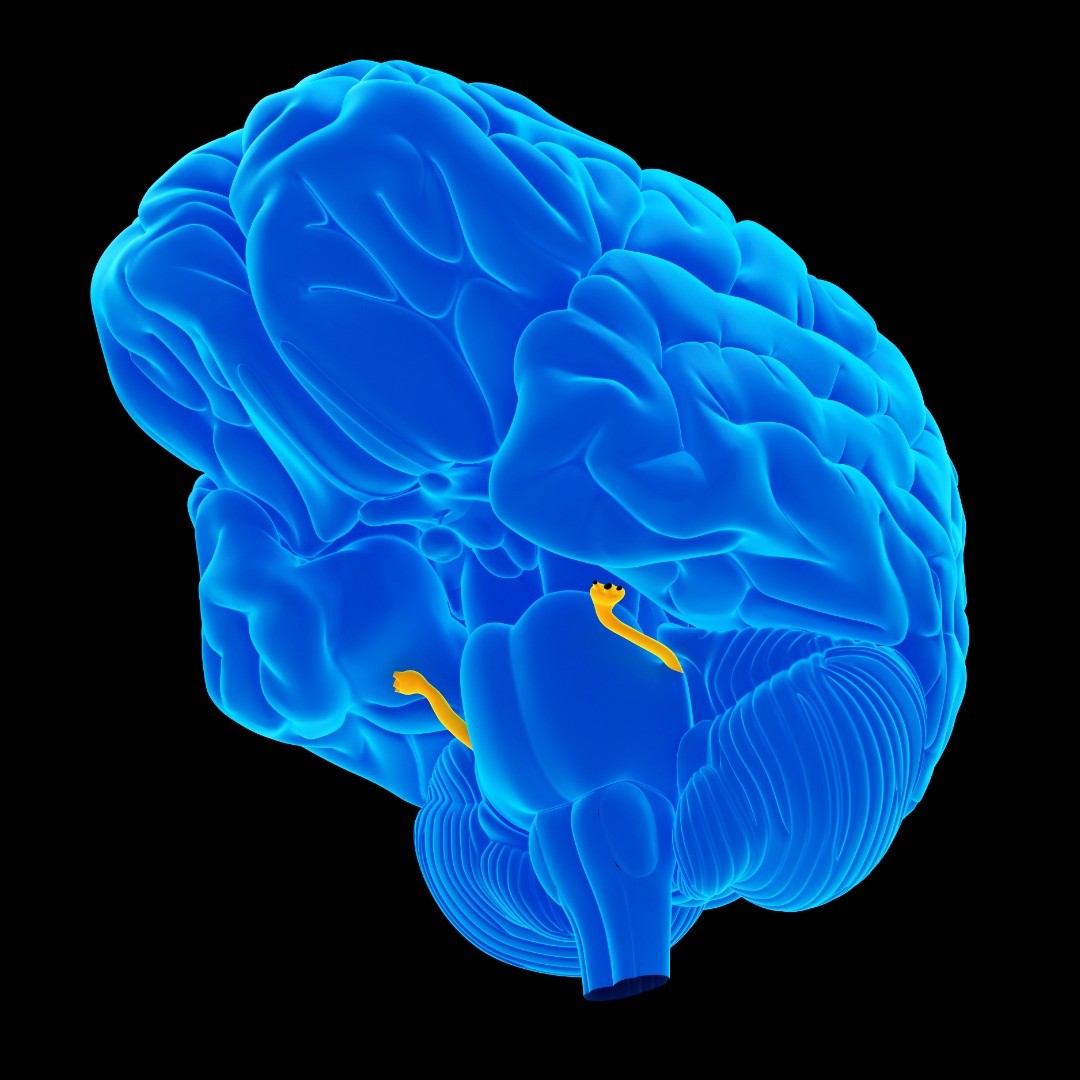

Microvascular decompression is brain surgery to remove pressure (decompression) caused by a very small blood vessel (microvascular) on a cranial nerve, usually the trigeminal nerve.

Microvascular Decompression is used to treat refractory (difficult to treat or unmanageable) facial pain or facial spasms caused by a compressed nerve: